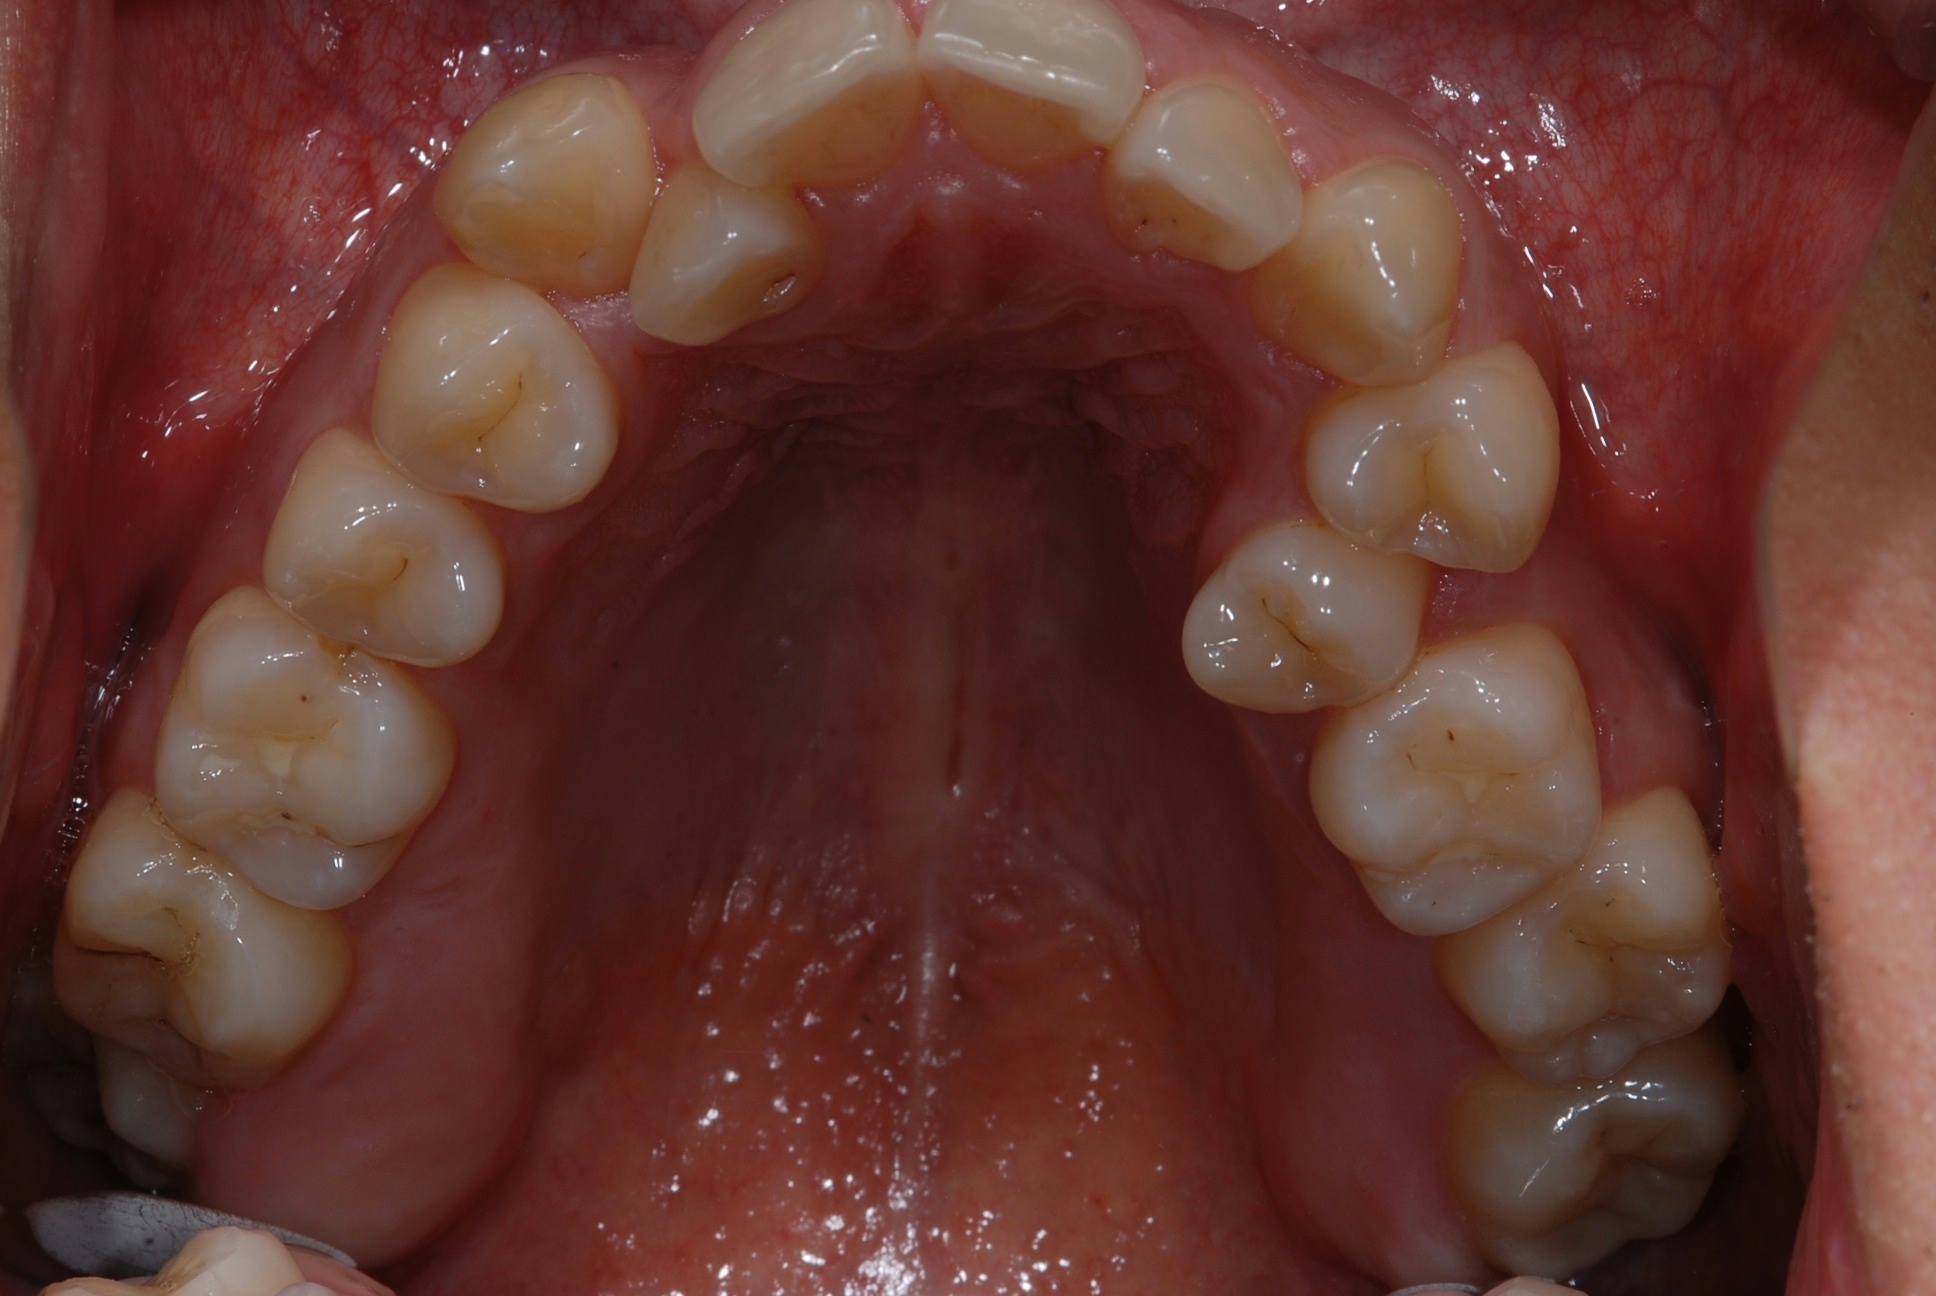

치료 전 사진입니다.